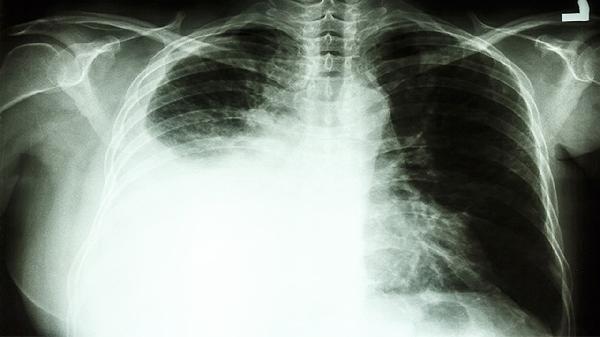

3、慢性支气管炎

慢性支气管炎患者在急性加重期常出现咳嗽咳痰加重、喘息等表现,与气道炎症反应和黏液过度分泌有关。清肺化痰丸可辅助控制症状,但需联合抗生素等西药治疗感染。长期吸烟者应戒烟,并接种肺炎球菌疫苗预防复发。用药期间需监测痰液性状变化,如转为脓性痰提示可能合并细菌感染。